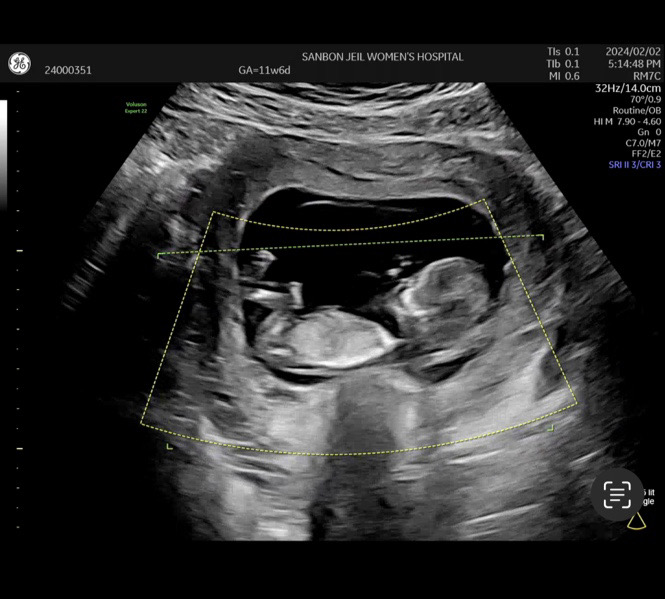

각도법 궁금해요^^

어때 보이시나요. ??